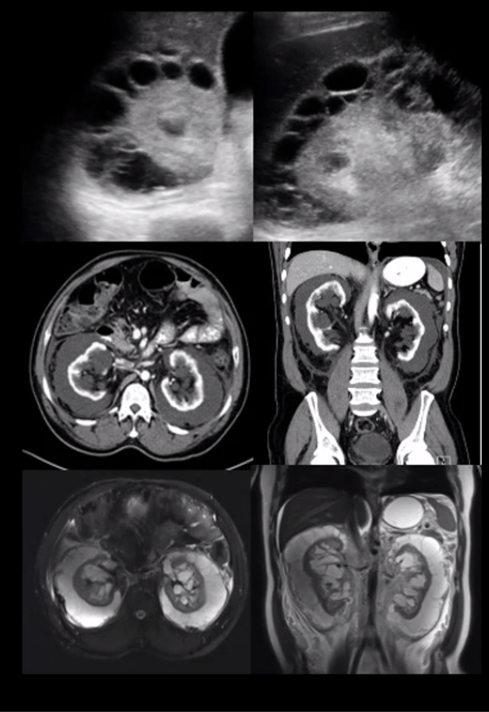

medullary nephrocalcinosis

bosniak classifcation?

2F